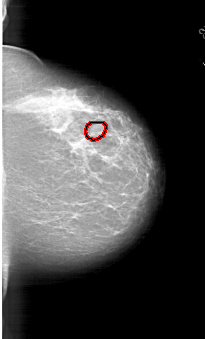

A_1767_1.RIGHT_MLO

RIGHT_CC LINES 6091 PIXELS_PER_LINE 3691 BITS_PER_PIXEL 12 RESOLUTION 43.5 OVERLAY

FILE: A_1767_1.RIGHT_CC.OVERLAY

TOTAL_ABNORMALITIES 1

ABNORMALITY 1

LESION_TYPE MASS SHAPE OVAL MARGINS CIRCUMSCRIBED

ASSESSMENT 3

SUBTLETY 3

PATHOLOGY BENIGN

TOTAL_OUTLINES 1

BOUNDARY